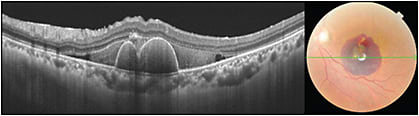

Swept-source (SS) technology is another new approach to better image the choroid (DRI-OCT Triton; Topcon). It utilizes a longer 1,050 nm wavelength at a scanning speed of 100,000 A-scans/second. The faster scanning speed reduces artifacts due to eye movement, allowing more data with more detail to be collected. The longer wavelength is invisible, increasing patient comfort. Standard OCT utilizes wavelengths in the 800 nm to 870 nm range, with less penetration into the choroid. The longer wavelength reduces the scatter reflection of the RPE, enabling SS-OCT to show clearer details of the deeper portions of the choroid, and with increased patient comfort, it facilitates more stable fixation. The longer wavelength also penetrates more effectively through media opacities (Figure 3) and hemorrhage (Figure 4).11,12

Using the wide-field protocol, SS-OCT enables the disc and macula to be imaged in a single scan. This allows clinicians to assess the relationship of disease in the nerve and macula without having to look at separate scans taken with possibly different head positions and eye alignments (Figure 5). SS-OCT can show details of the vitreous, retina, and choroid simultaneously. SS-OCT can better highlight the vitreomacular interface (Figures 6, 7). Unlike with EDI-OCT that requires either the vitreous or the retina to be at focus, SS-OCT has a much larger depth of imaging that enables more detailed imaging of the vitreous.